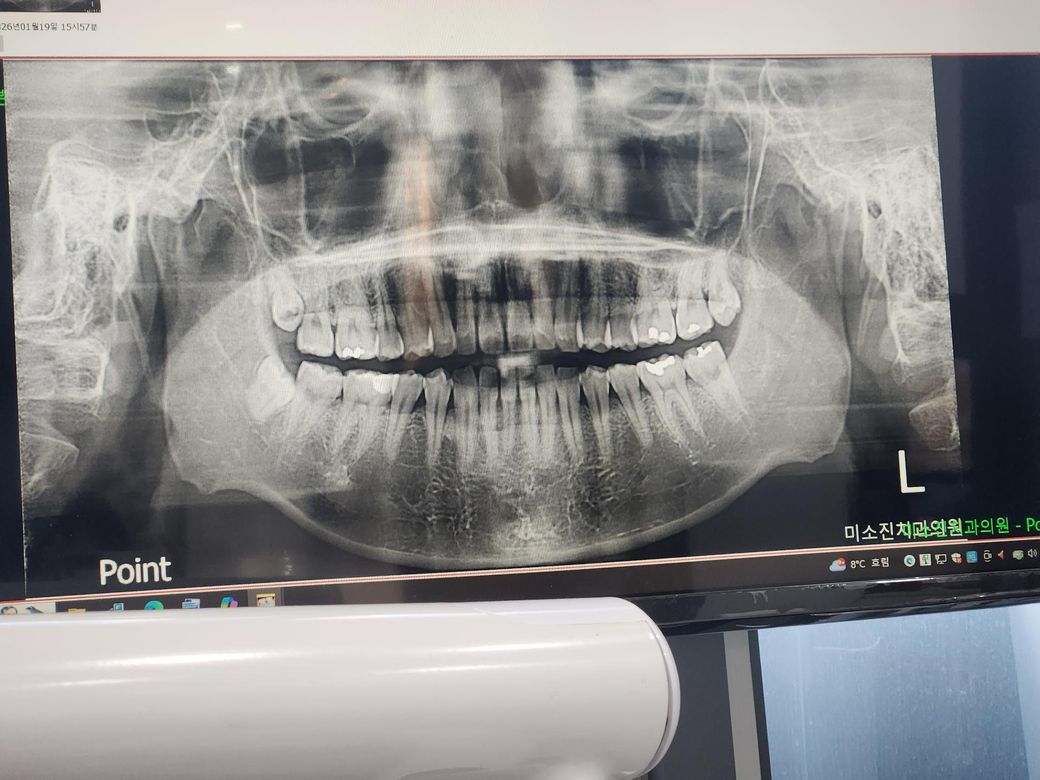

한달전쯤 찍은 xray사진인데 이걸보고 충치 판별이 가능하실까요? 찬물먹고 머금으면 왼쪽 위 어금니가 시리네요. 사진을 정면으로 봤을때 기준 오른쪽 위 어금니쪽 입니다.

왼쪽 위 두번째 작은어금니(5번째 치아)의 사이 충치가 의심되긴합니다. 엑스레이 작은 사진도 찍어보세요

사진으로는 정확한 충치의 여부를 확인하기느 어려워 보입니다. 정확한 확인을 위해서는 육안으로 확인이 필요할것으로 생각됩니다.

자세한 확인을 위해서 치과에서 진료를 받아보는 것을 권유드립니다.